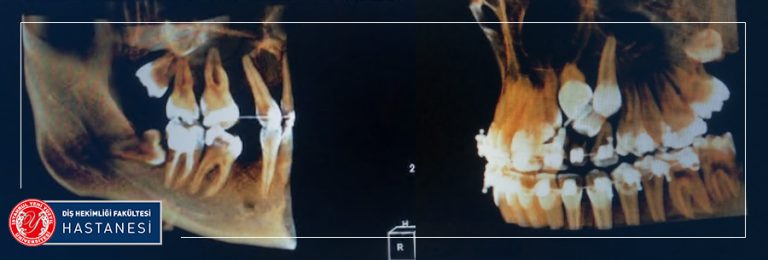

Hastaların fakülteye ilk başvurularında muayenelerinin yapıldığı bölüm Ağız Diş ve Çene Radyolojisi bölümüdür. Ağız, Diş ve Çene Radyolojisi’ne bağlı Oral Diagnoz bölümümüzde; tüm dişler ve ağız içi dokular değerlendirilir. Henüz şikayet olmayan dişlerle ilgili müdahaleler gerekiyorsa, bilgilendirme yapılmaktadır. Hastalıkların teşhis ve tedavilerinde genellikle görüntülenmesi de gerekli olmakta ve bu görüntüleme yöntemleri ve ayrıca diğer kliniklerin ihtiyacı olan radyografi ihtiyaçları da Radyoloji kliniğimizde karşılanmaktadır. Çekilen radyograflar; Gözle yapılan muayenede farkedilmeyen çürük alanlarının, Dolgu altında gelişen yeni çürüklerin, Hijyenik olmayan restorasyonların araştırılmasında, Dişeti hastalıklarında kemik kaybının derecesinin belirlenmesinde, Kanal tedavilerinin başında ve sürecinde, İmplant uygulamalarında kemiğin araştırılmasında, Ortodontik tedavilerin başında ve sürecinde, Çocuklarda diş gelişim ve büyümesinin izlenmesinde, Kemik dokuda ki kist, tümör gibi patolojilerin belirlenmesinde yardımcıdır. Gerekli görüldüğünde ileri görüntüleme ve tetkikler için Tıp hekimliği branşlarından faydalanılmaktadır. Bu bilgilerin ışığında bireye özgü tedavi planı hazırlanmakta ve bu tedavilerin yapılacağı uzman kliniklere hastalar yönlendirilmektedir